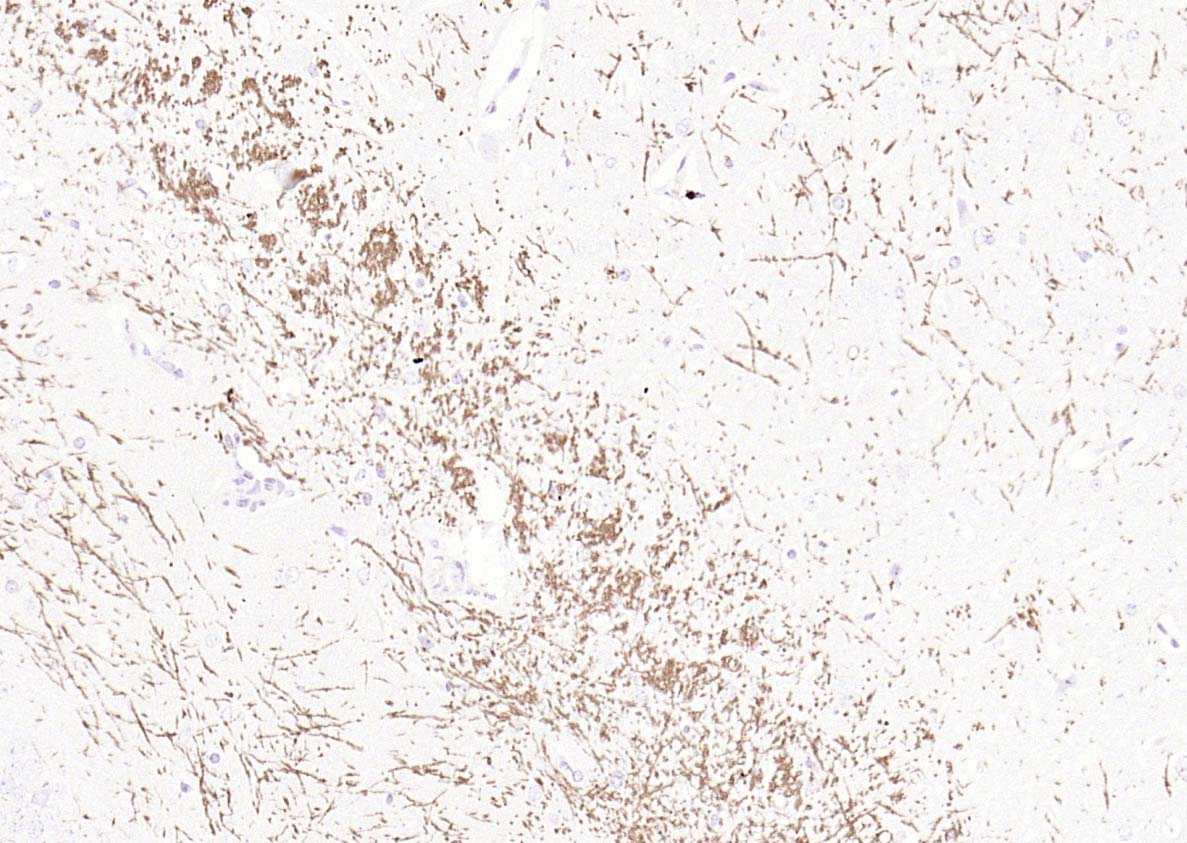

The protein encoded by the classic MBP gene is a major constituent of the myelin sheath of oligodendrocytes and Schwann cells in the nervous system. However, MBP-related transcripts are also present in the bone marrow and the immune system. These mRNAs arise from the long MBP gene (otherwise called "Golli-MBP") that contains 3 additional exons located upstream of the classic MBP exons. Alternative splicing from the Golli and the MBP transcription start sites gives rise to 2 sets of MBP-related transcripts and gene products. The Golli mRNAs contain 3 exons unique to Golli-MBP, spliced in-frame to 1 or more MBP exons. They encode hybrid proteins that have N-terminal Golli aa sequence linked to MBP aa sequence. The second family of transcripts contain only MBP exons and produce the well characterized myelin basic proteins. This complex gene structure is conserved among species suggesting that the MBP transcription unit is an integral part of the Golli transcription unit and that this arrangement is important for the function and/or regulation of these genes.

| IHC-P | Human, Mouse, Rat | Rabbit, Pig, Sheep, Cow, Dog, Horse | 1:500-2000 |